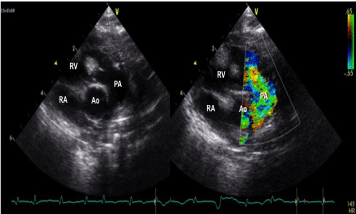

In April 2006, an apparently healthy male newborn was diagnosed to have signs of biventricular hypertrophy and sporadic ventricular premature beats of two morphologies, originating from the left ventricular apex and the RVOT. No foetal echocardiographic evaluation was accomplished at that time. The echocardiographic evaluation performed shortly after birth showed numerous large “echodense” masses localized intramurally in the left and right ventricle, compatible with multiple rhabdomyomas. The cavity was completely obliterated by three large masses localized at the left ventricular apex (Figure 1). Left and right ventricular mid cavities were almost entirely occupied by other masses (Figure 2). A large mass caused a significant obstruction of the LVOT with an intraventricular gradient of 47 mmHg (Figure 3). Another lesion, detected in the RVOT very close to the pulmonary valve, was responsible for a mild flow acceleration without significant gradient (Figure 4). The mitral pattern at pulsed wave Doppler evaluation showed signs of impaired left ventricular diastolic function (Figure 5).

Figure 4. A large rhabdomyoma detected in the right ventricular outflow tract, very close to the pulmonary valve, responsible for mild flow acceleration without significant gradient

Figure 5. Anomalous mitral pattern at pulsed wave Doppler evaluation showing signs of impaired left ventricular diastolic function